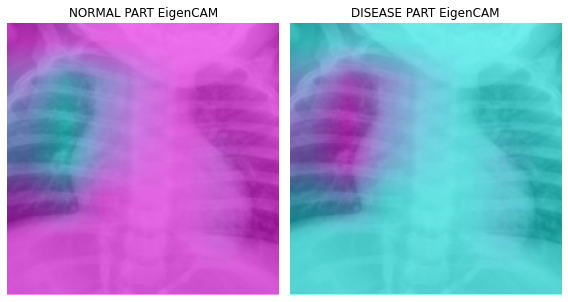

fig, (ax1,ax2) = plt.subplots(1,2)

dls.train.decode((x,))[0].squeeze().show(ax=ax1)

ax1.imshow(-cam_eigencam.squeeze(),alpha=0.5,extent=(0,224,224,0),interpolation='bilinear',cmap='cool')

ax1.set_title("NORMAL PART EigenCAM")

#

dls.train.decode((x,))[0].squeeze().show(ax=ax2)

ax2.imshow(cam_eigencam.squeeze(),alpha=0.5,extent=(0,224,224,0),interpolation='bilinear',cmap='cool')

ax2.set_title("DISEASE PART EigenCAM")

fig.set_figwidth(8)

fig.set_figheight(8)

fig.tight_layout()